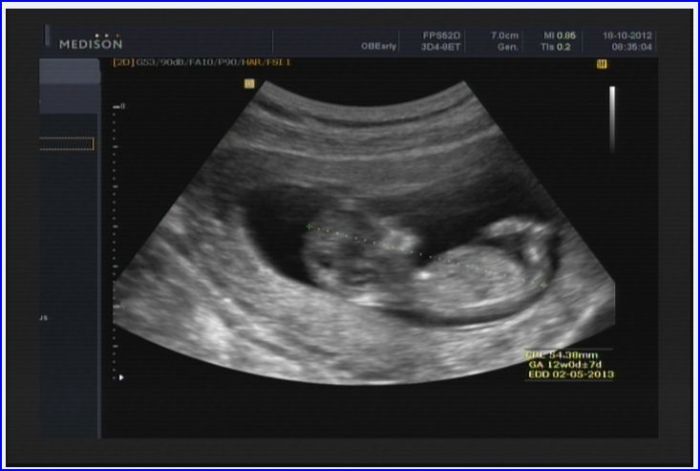

Takže tedy, jak jsem psala, všechno je krásně na tom UZV vidět, je legrační, jak se moc mrňousek hýbe, je to cvalík čipera:o) 6.11. jdu ještě jednou na krev, kvůli znovu potvrzení vyloučení Down syndromu (teď byly výsledky krve OK) a 13.11. na kontrolní UZV, protože výsledky krve se vždy párují s UZV, jinak je to prý nevypovídající. Pan doktor mi řekl, že je vše v pořádku, výsledky krve také – větší podrobnosti mi neřekl, jen že ta první krev se bere na vyloučení HIV, syfilis, žloutenky a protilátek. Dělal tím UZV také projasnění šíje, ale z toho my laici fakt nic nepoznáme:o) akorát jsem krásně viděla obě čelisti mrňouska:o) Pro představu posílám fotečku z UZV, má krásný bříško cvalík:o) Byla jsem včera opravdu šťastná jak blecha a pořád se mě to drží a prohlížím si jeho fotky:o) Rodiče byli nadšení, možná i „překvapený“, ale měli hroznou radost! Držím vám všem holky palce, ať vám to taky dopadne dobře!!!

Přikládám tu fotku, měl brouček pokrčený nožičky momentálně....prostě na pohodu